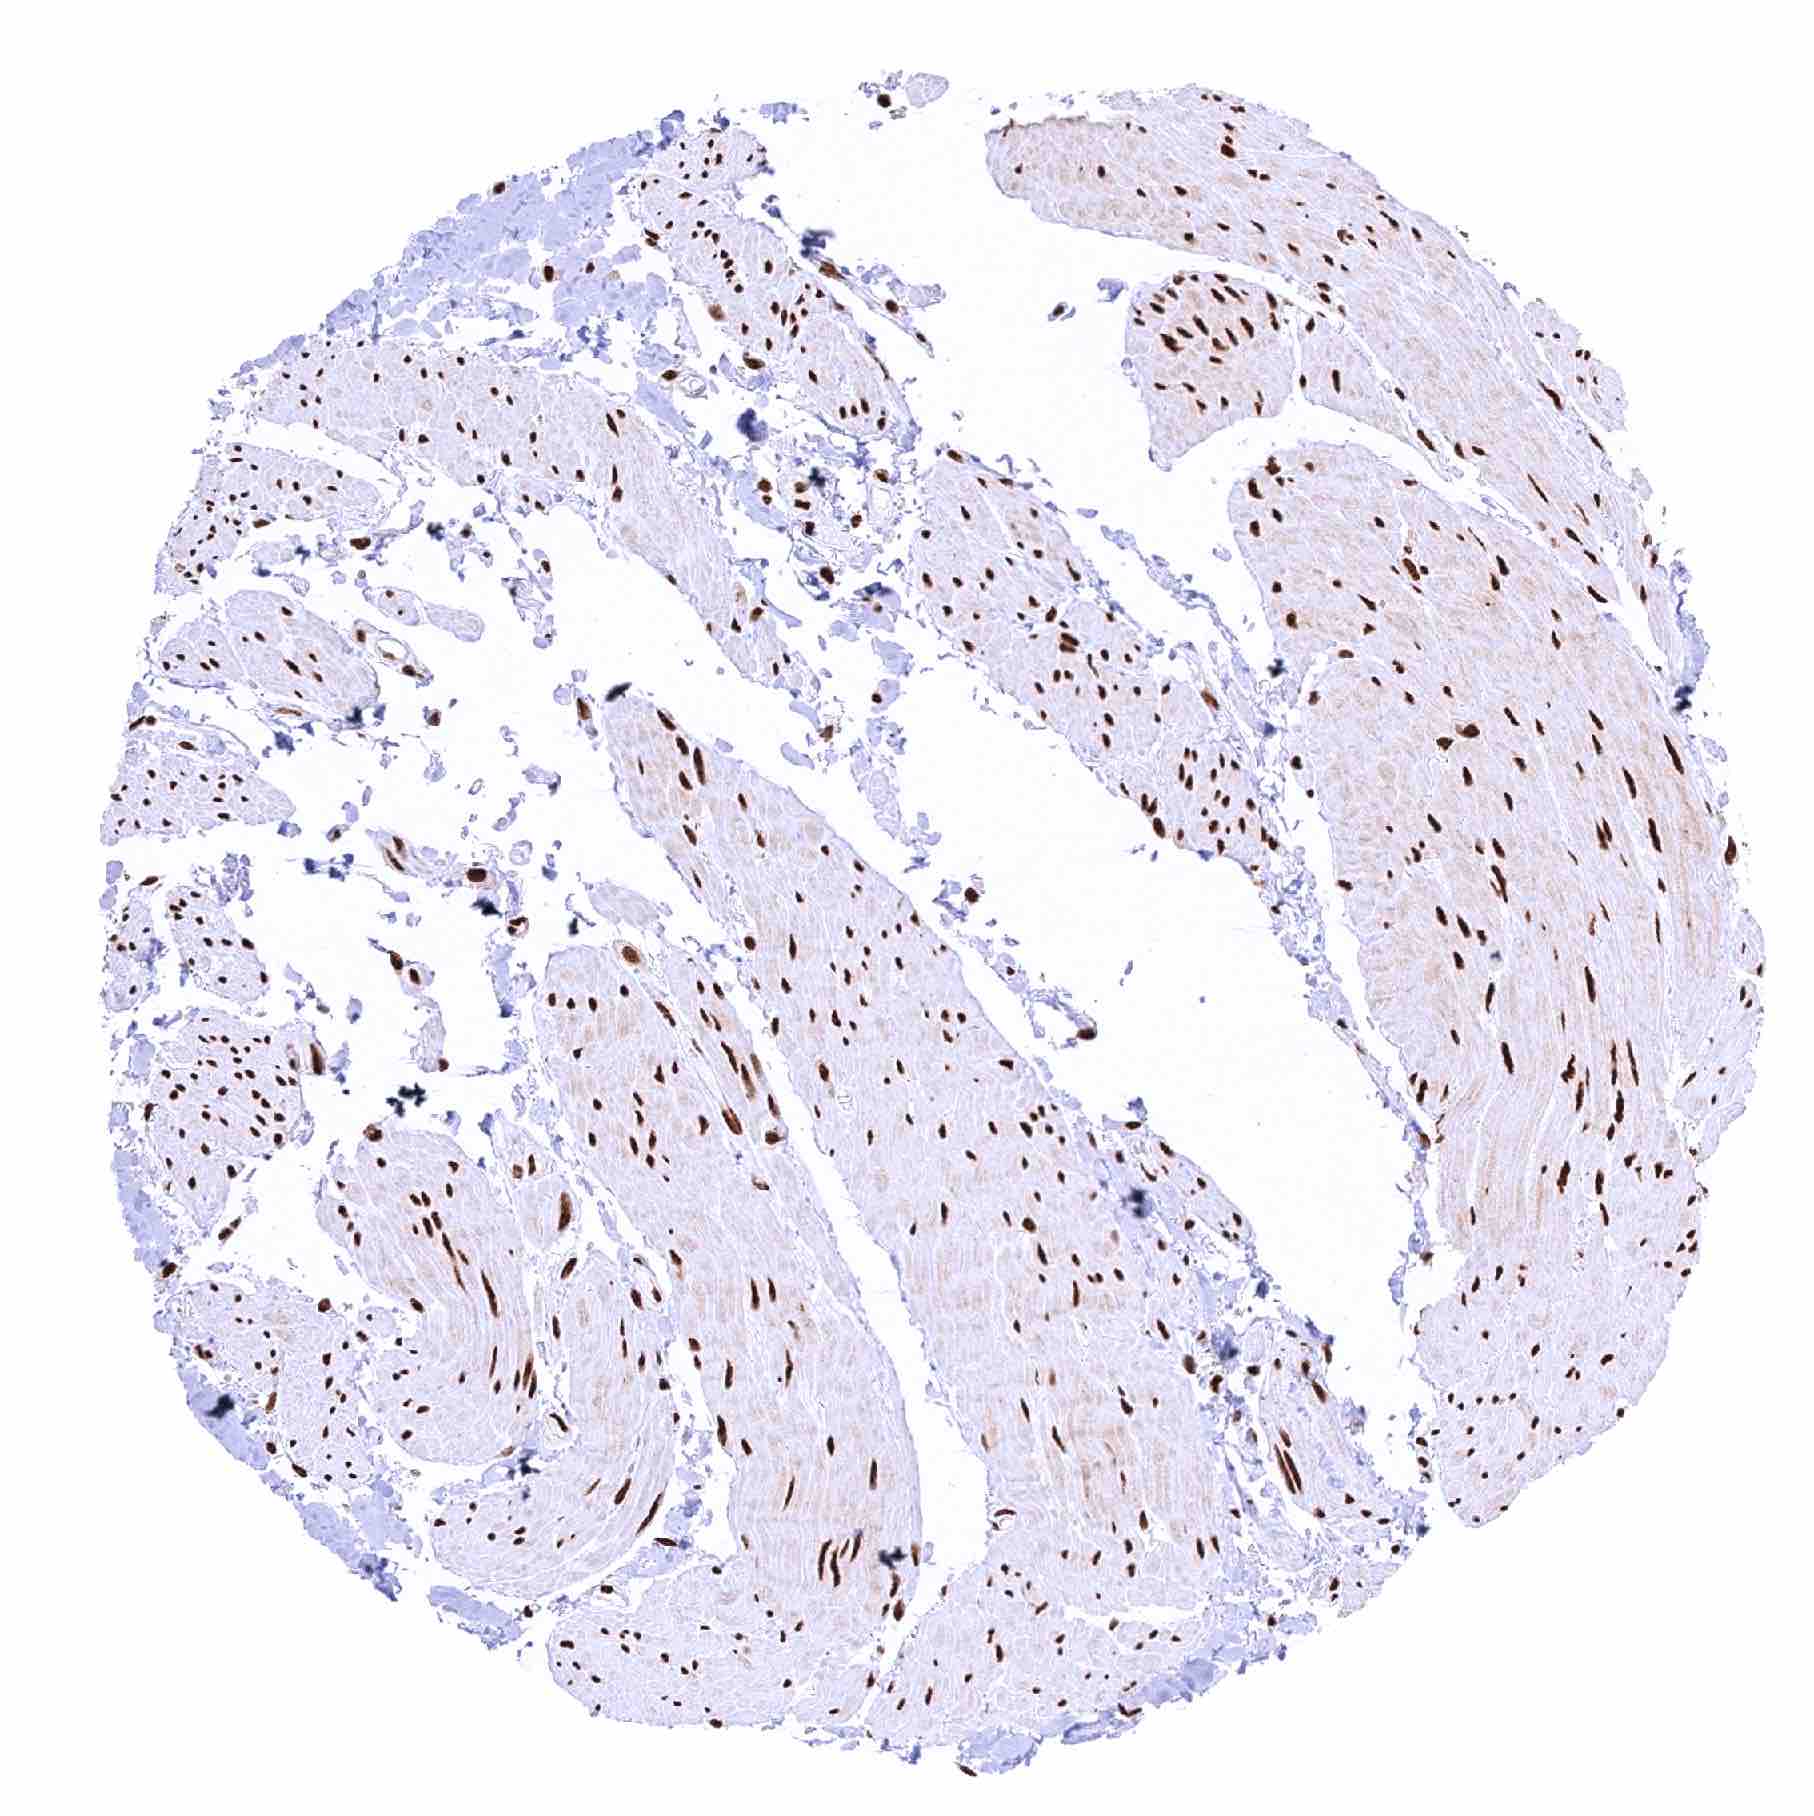

Skeletal muscle – Strong nuclear MRE11 staining of all cells